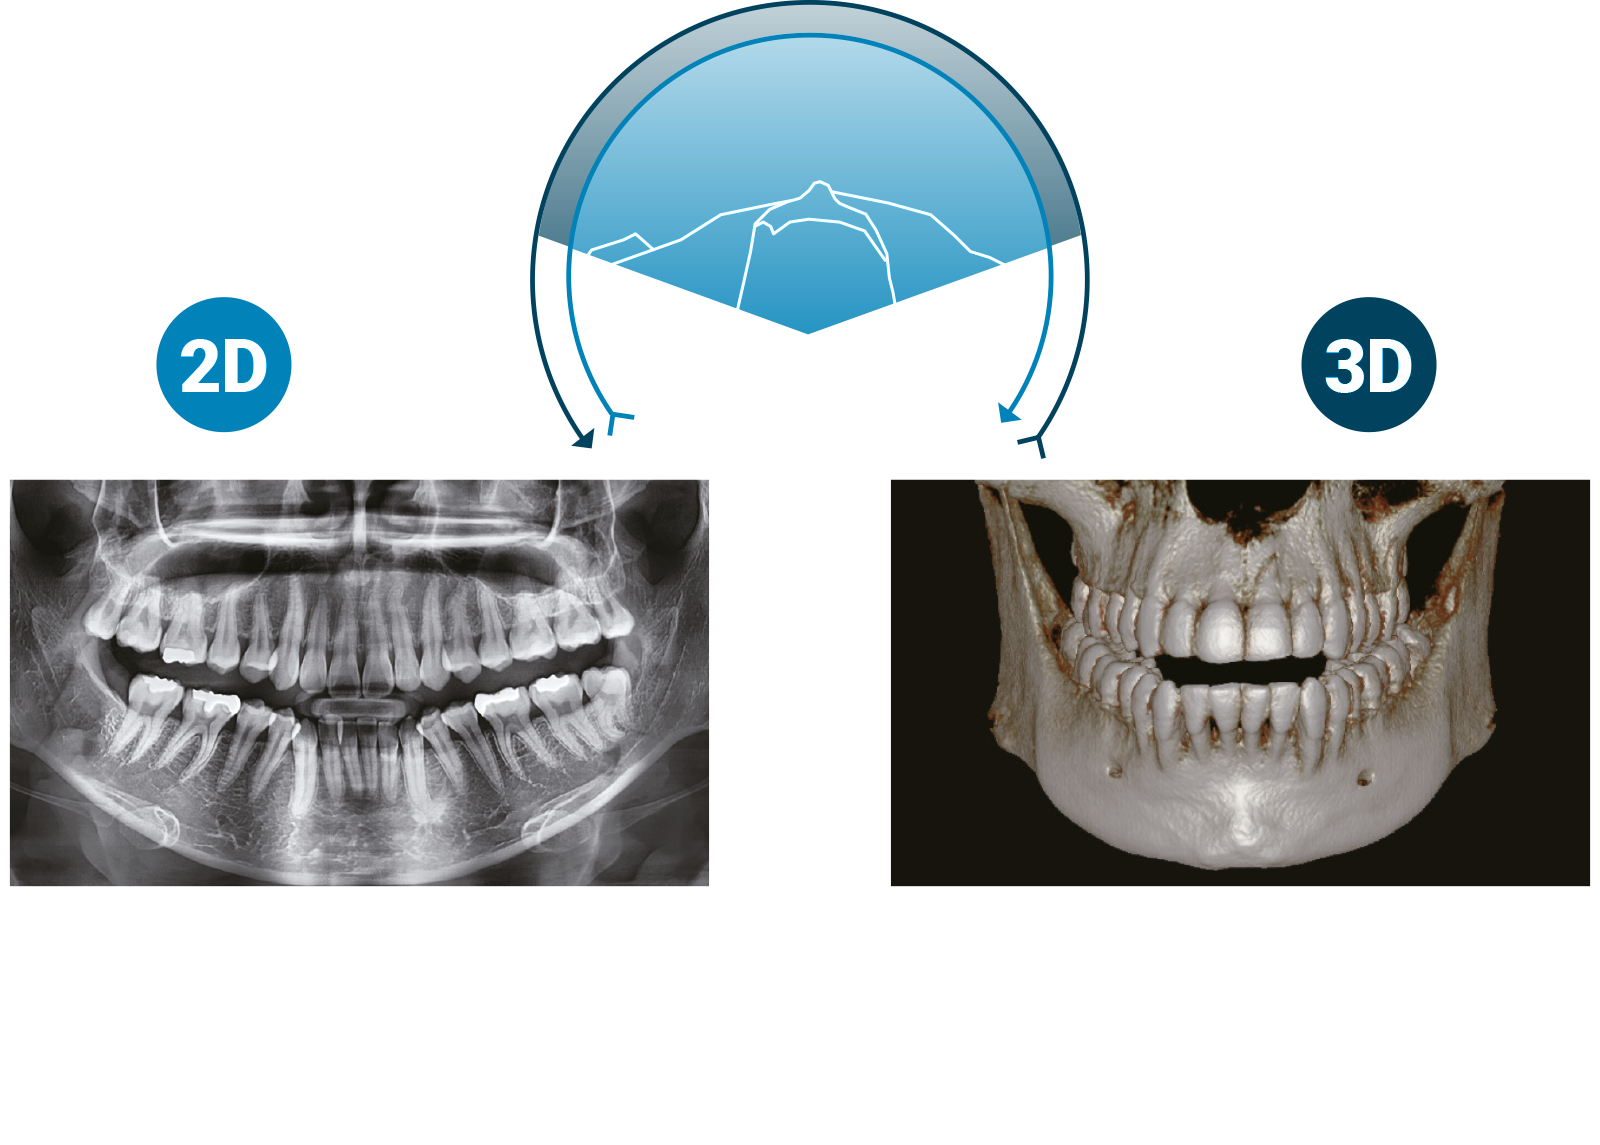

1 SCANSIONE, 2 IMMAGINI

MULTI AFOV

Multi anatomical Field Of View

Endodonzia5x5

Il massimo della versatilità grazie alla funzione esclusiva del Pax-i 3D Smart: MULTI AFOV. Forme geometriche o strutture anatomiche, con il nuovo concetto di volume di Pax-i 3D Smart, si ottiene il massimo risultato diagnostico con il minimo volume possibile.

A partita di FOV, la forma cilindrica può escludere parti importanti della scansione.

Il FOV anatomico di 3D Smart (o Multi AFOV) è ottenuto grazie al percorso meccanico, progettato per eseguire un movimento complesso su tre fulcri di rotazione, e l’elettronica.